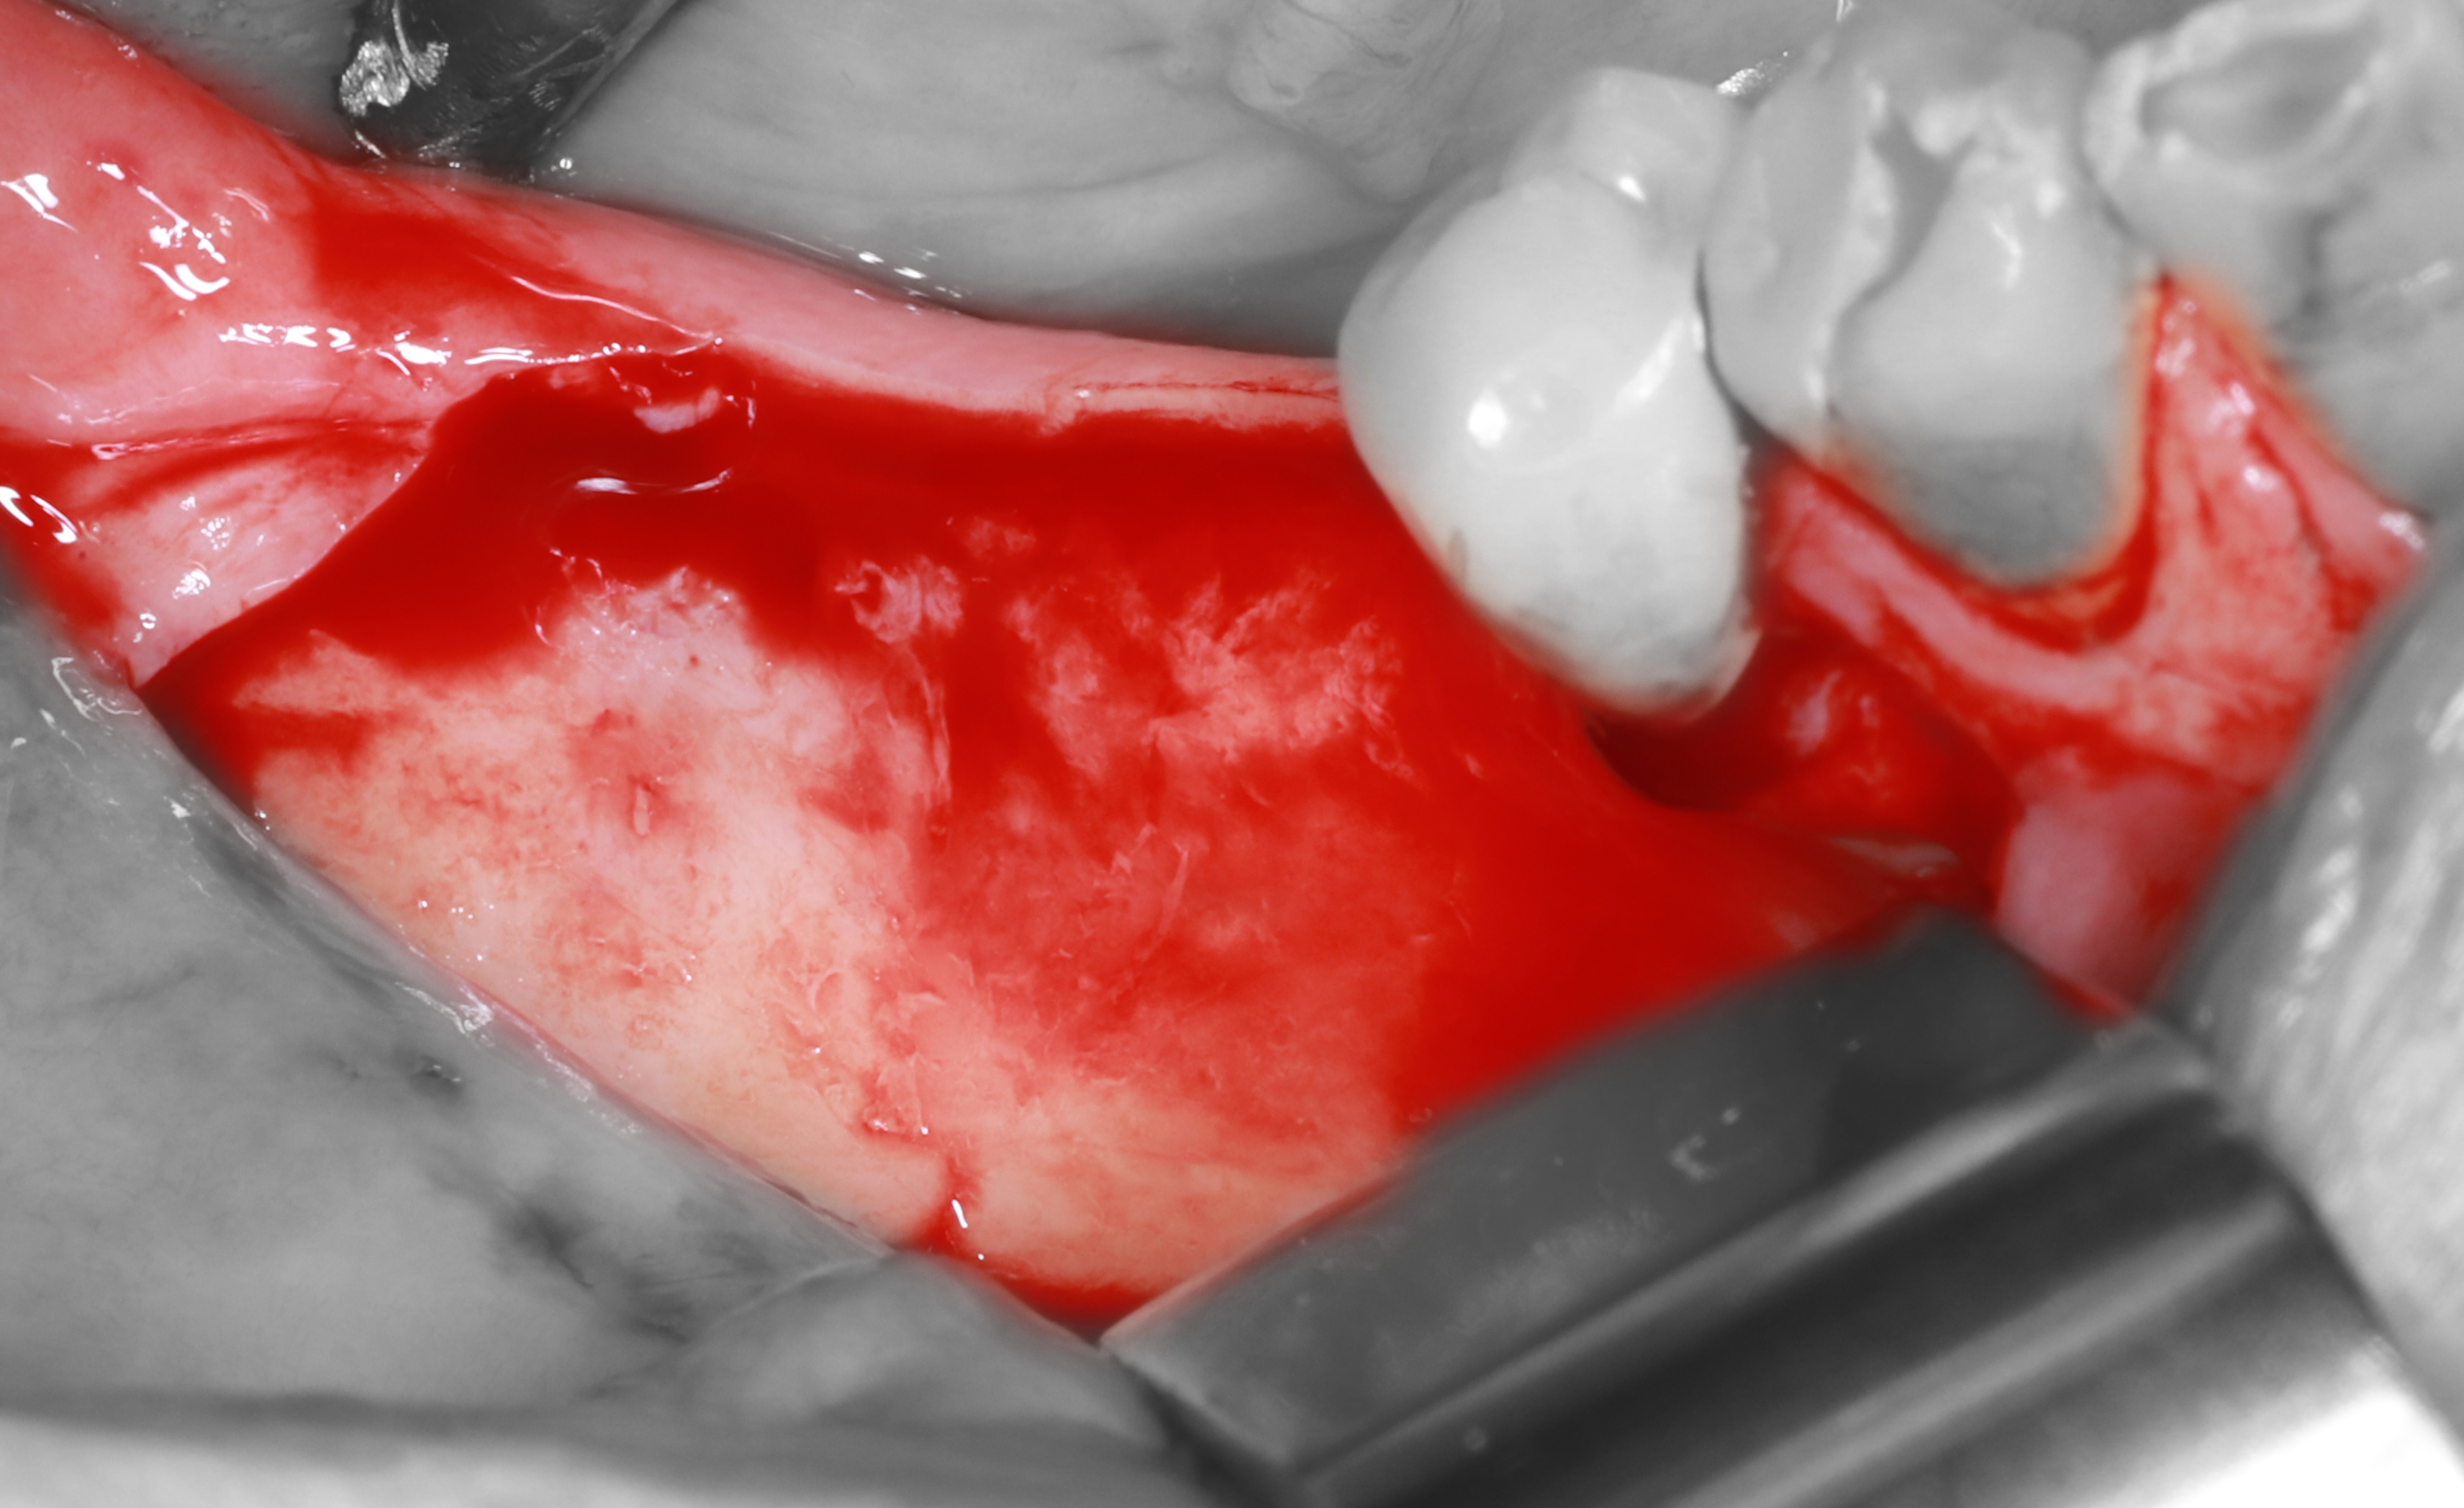

1) Латеральный дефект мягких и твёрдых тканей

2) Проведён разрез по гребню, отслоен СНЛ

5) Полученные костные трансплантаты (морковки)

8) Фиксирован дистальный костный трансплантат (морковь)